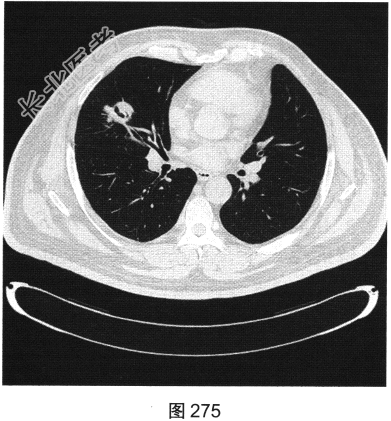

- [材料题] 患者男性,56岁,因“查体发现右肺中叶结节半个月余”就诊。患者于半个月前在小汤山疗养院查体时行胸部X线检查,显示右肺中叶结节,遂至我院就诊。行胸部CT检查:显示右肺中叶外侧段有一肿块影,大小为3.6cm×3.2cm,可见分叶,边缘有毛刺,内见空泡影,CT值约15HU,增强后CT值约25HU。患者近期无咳嗽、咳痰,无咯血、胸痛,无发热、乏力,无声音嘶哑、饮水呛咳,无头痛、头晕,未予特殊治疗。为进一步诊治,以“右肺占位”收入我院。患者精神状态良好,体力、食欲、睡眠正常,体重无明显变化,大、小便正常。胸部CT检查如图274~图277所示。

- 多项选择题1.患者病变的影像特点包括( )

A、右肺中叶结节

B、裂隙样空洞

C、界限清楚

D、血管集束征

E、病变轻度强化

F、可见卫星灶